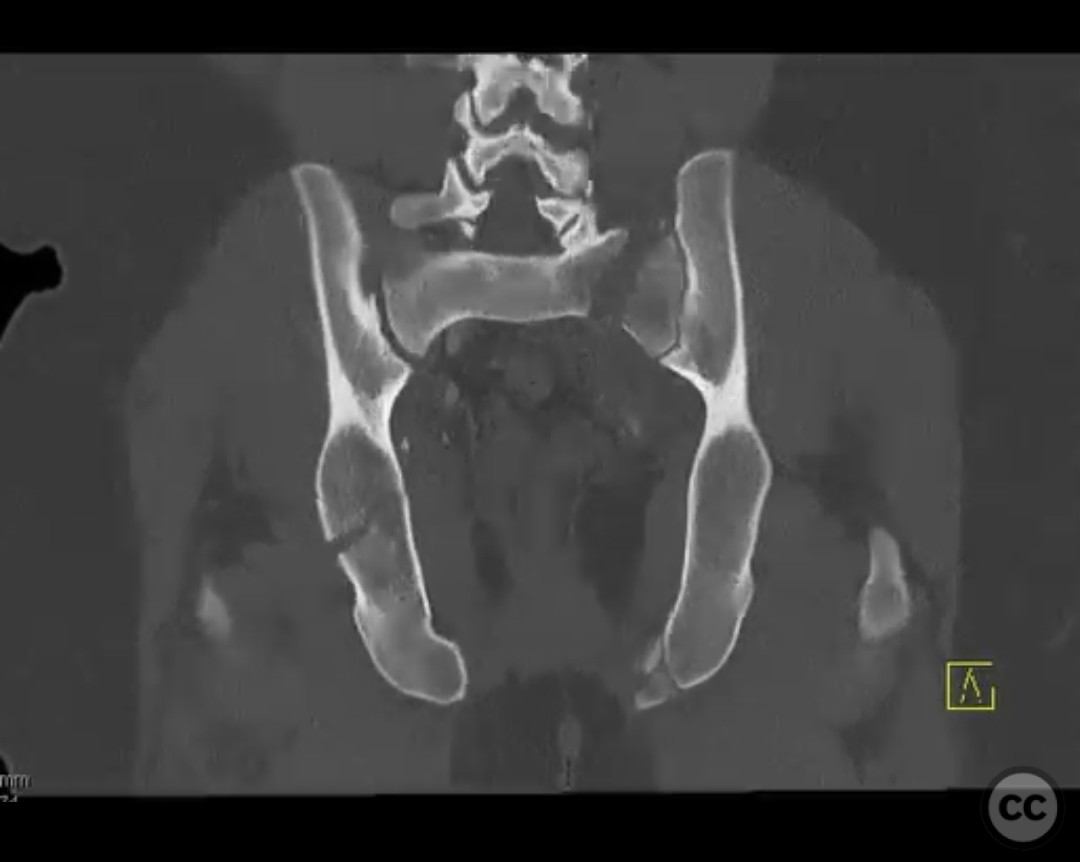

Clinical and radiological findings:  The patient presented with a highly unstable pelvic ring injury and a transverse acetabulum fracture, accompanied by a bladder injury. The bladder injury was addressed emergently with a low vertical midline Pfannenstiel incision for repair, followed by the placement of a low right-sided suprapubic catheter. Radiological imaging confirmed the transverse acetabular fracture and disruption of the left sacroiliac joint, along with a displaced sacral fracture.